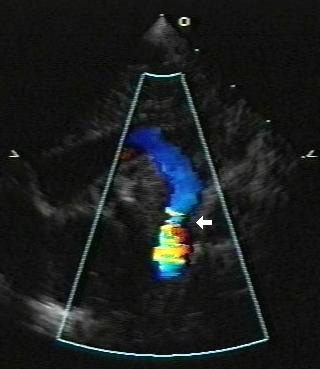

Addition of color Doppler shows turbulent higher velocity flow after the obstructed area

From the personal collection of Jeffrey Gossett, MD, Children's Memorial Hospital, Northwestern University, Chicago; used with permission